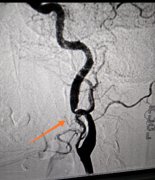

神經(jīng)內(nèi)科聯(lián)合介入中心首次成功開展全腦血管造影術(shù)

2020年7月20日對(duì)于我們神經(jīng)內(nèi)科來說是一個(gè)不平凡的日子,在醫(yī)院領(lǐng)導(dǎo)、介入中心和兄弟科室的大力支持下,成功為一名患者實(shí)...